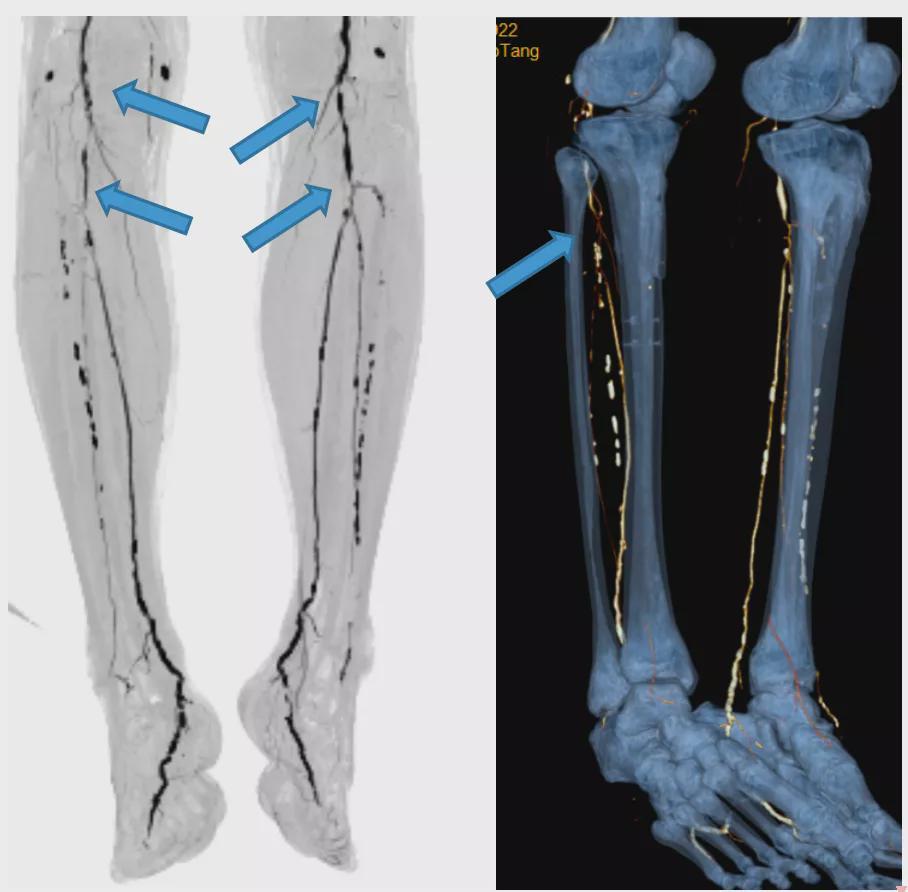

入院后完善下肢动脉CTA检查。

CTA提示患者双下肢动脉多发狭窄或闭塞,而引起肢体缺血症状,导致右足伤口反复不愈合。在我科杜端明主任的带领下,经科内多名专家进行全面评估后,决定对患者行介入微创治疗,吴育民副主任医师为主刀,江磊昌主治医师为一助,通过顺行穿刺下肢股动脉,对狭窄闭塞的动脉进行开通。